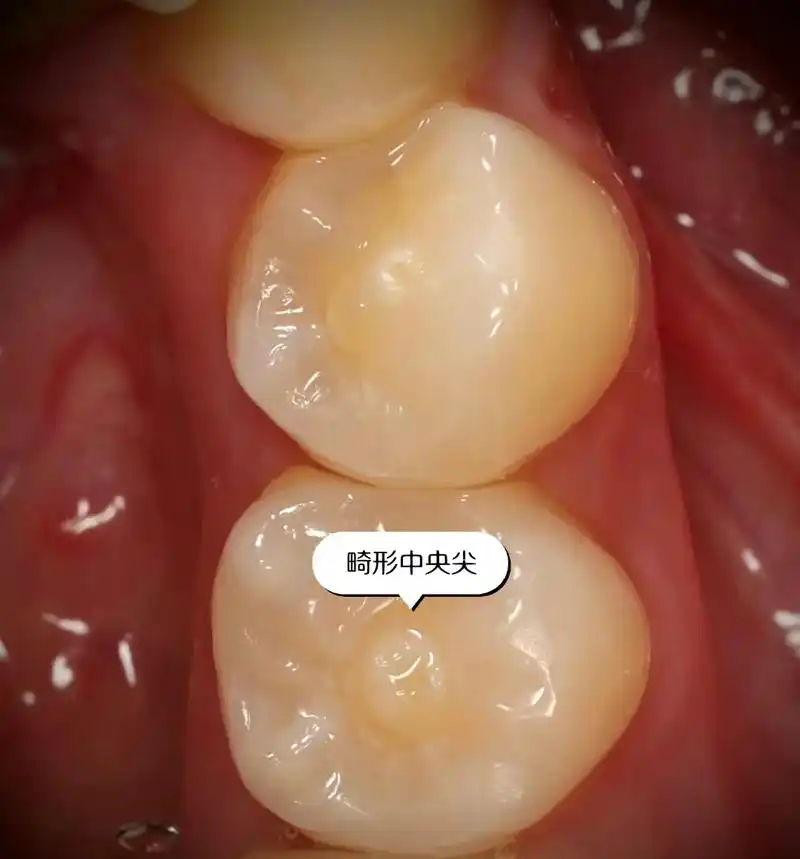

牙齿中间的小尖尖.